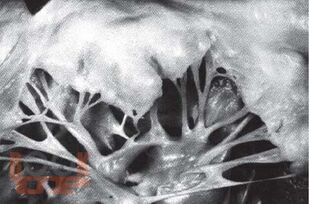

В книге подробно изложены этиология, клиника, дифференциальная диагностика и вопросы лечения пролапса митрального клапана у детей. Приводятся клинические варианты пролабирования в зависимости от тяжести соединительнотканной дисплазии и миксоматозной дегенерации.